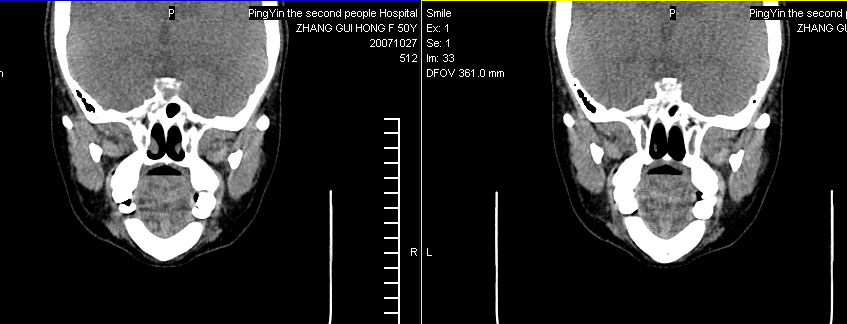

标题: CT10219:蝶鞍区有无异常?

女。50岁.头疼恶心半月余.双上颌窦区压疼明显,曾有高血压.现基本控制.

有问题,双侧侧脑室扩大,感觉鞍区有肿块,建议增强扫描.

感觉鞍区异常,建议增强扫描.